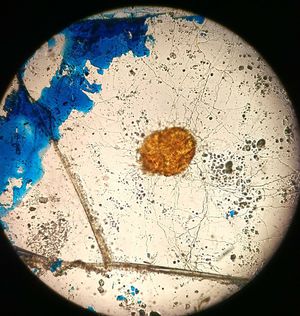

Is it a neuron?????

its an organism

Giardia

Sarcoptes

Sarcopti scabii??

S.scabii

I thought it was a tick

Ascaris🤔

Scabies

Sarcoptes scabies